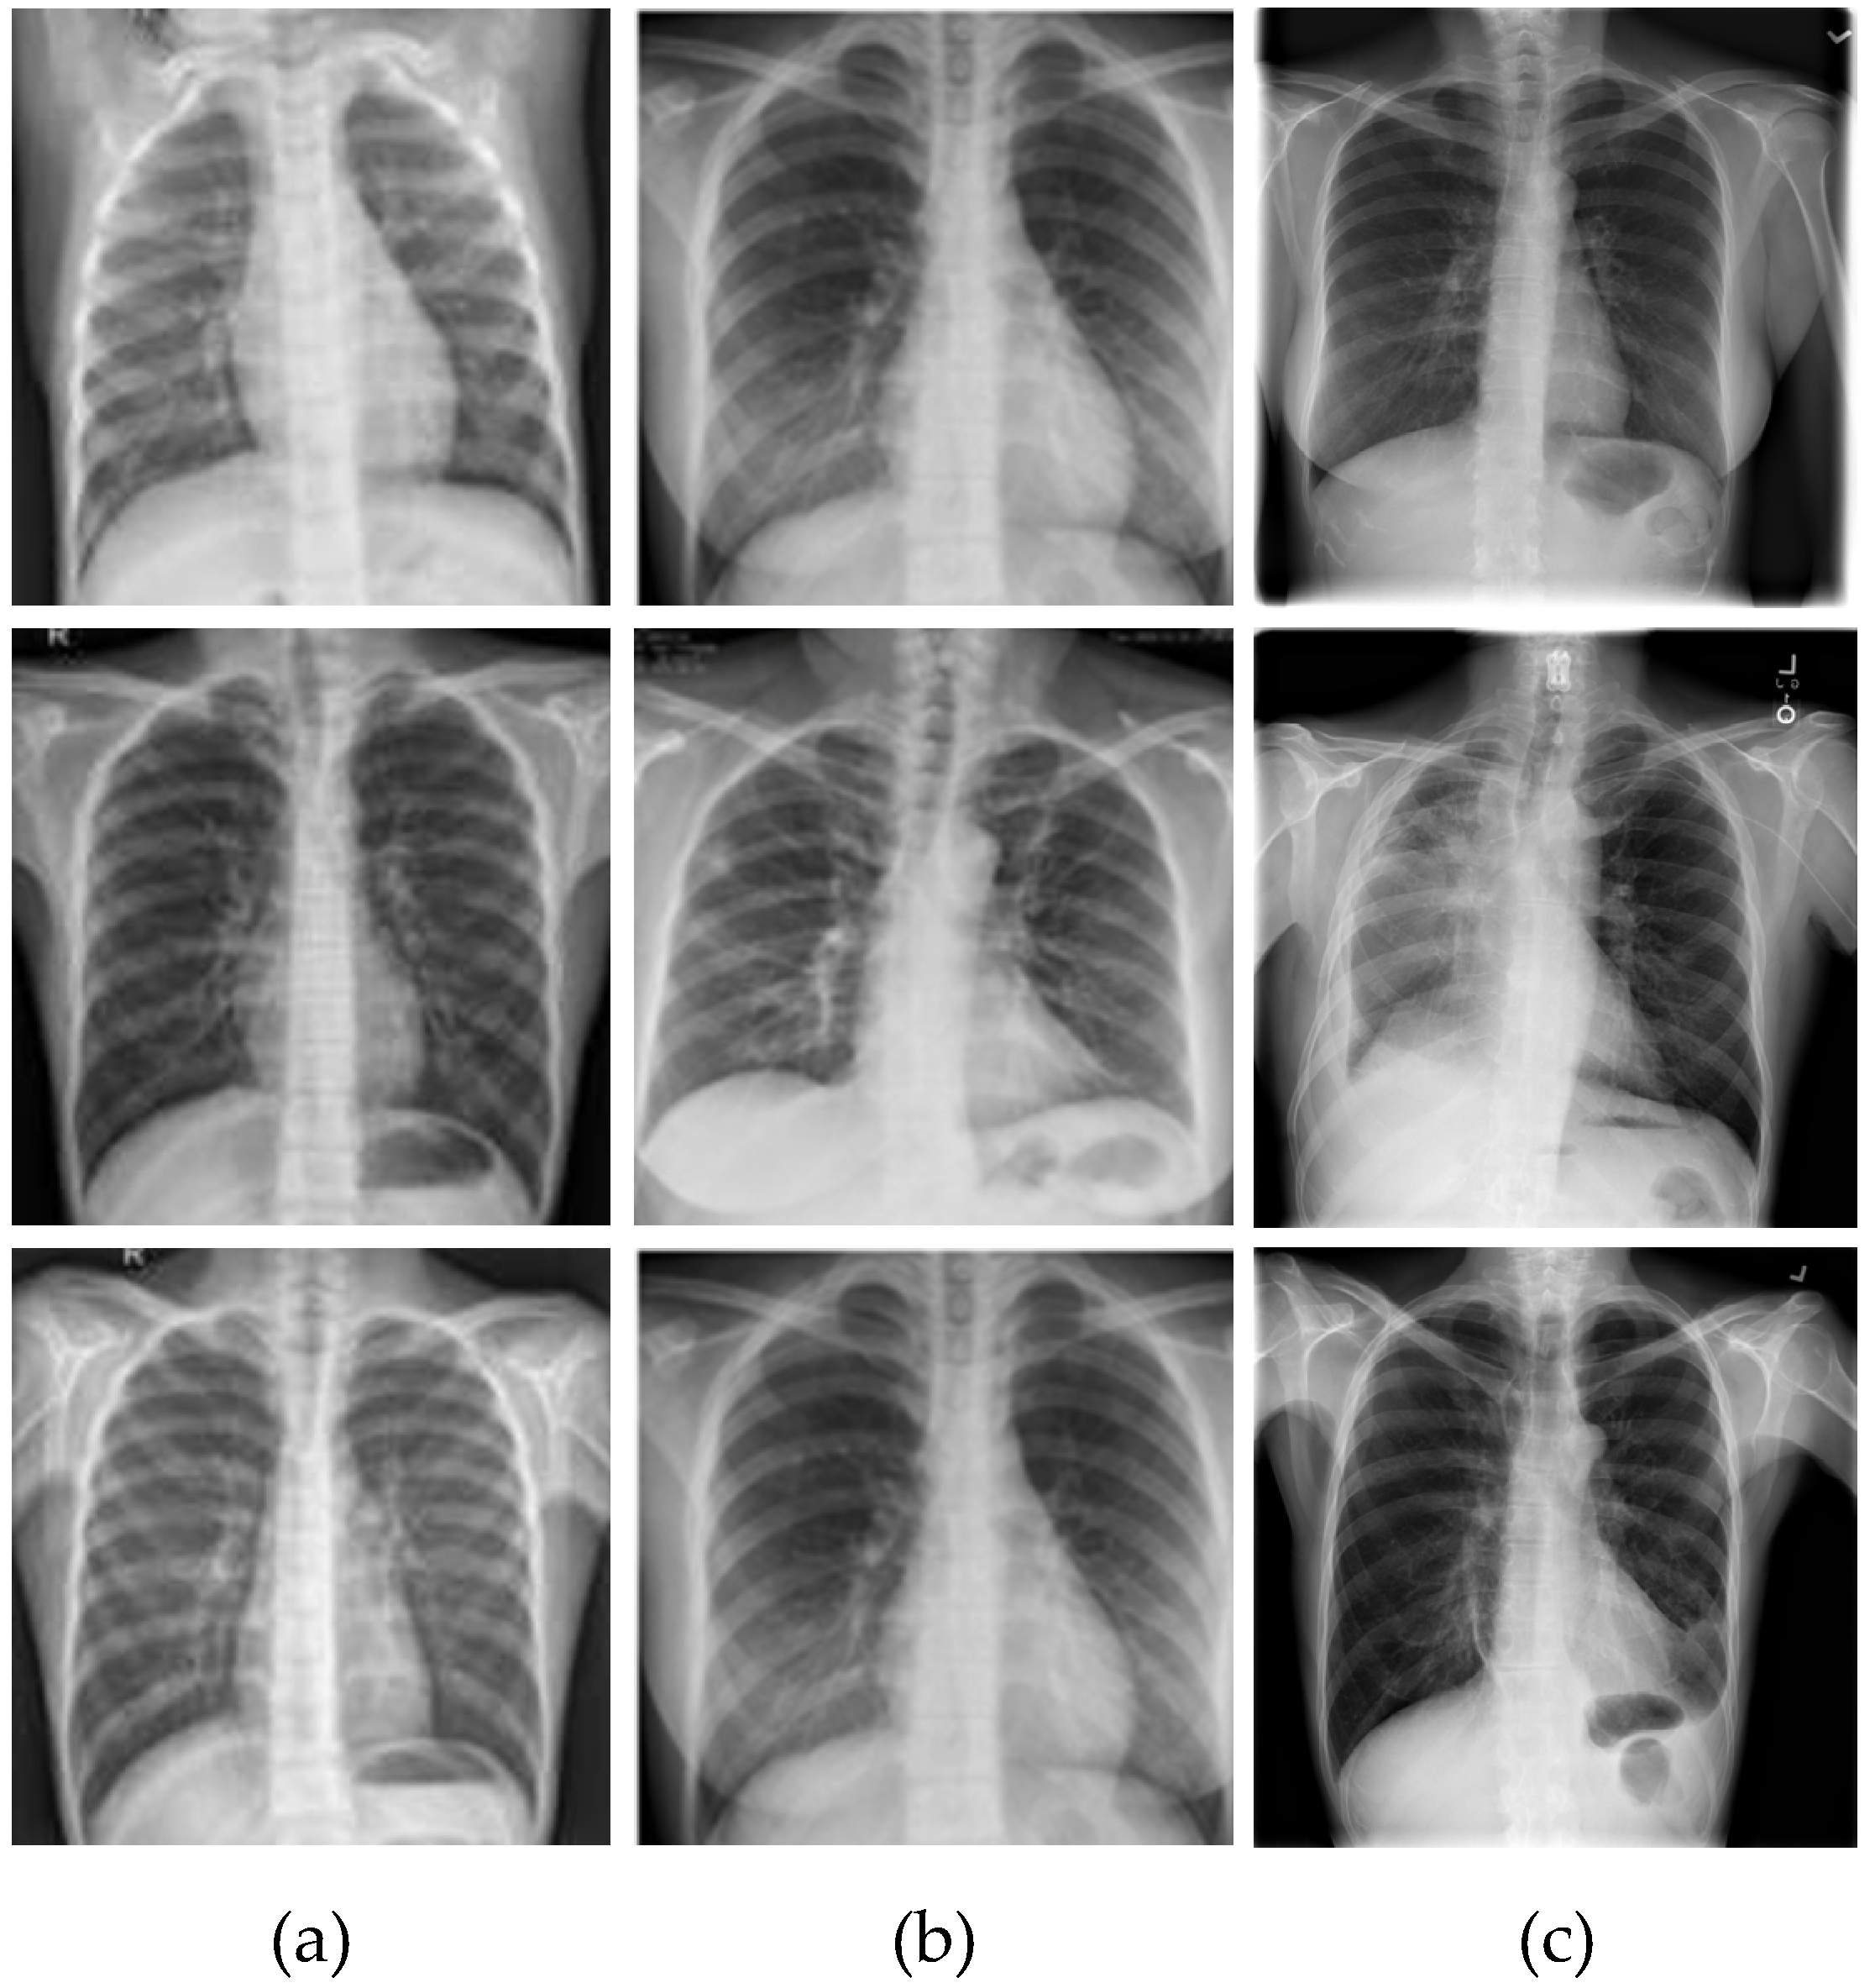

3. Dataset